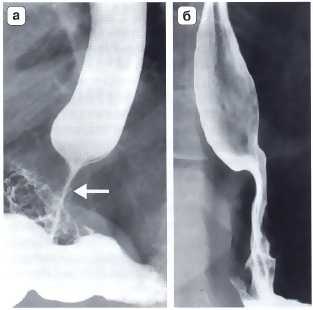

Рис. 3. Рентгенограмма. Осложнения после фундопликация по Ниссену. а — дисфагия, обусловленная излишне туго сформированной манжеткой; б — дисфагия, вызванная излишне длинной фундопликационной манжеткой. В обоих случаях видны признаки нарушения проходимости в области пищеводно-желудочного перехода и супрастенотическое расширение пищевода выше наложенной манжетки (Черноусов А.Ф. и др.)

Другим важным и довольно частым осложнением операции фундопликации по Ниссену является соскальзывание кардиального отдела и дна желудка с терминальным отделом пищевода относительно манжетки (рис. 4, б). Как правило, причиной этому служит прорезывание швов между манжеткой и пищеводом. Ушивание ножек диафрагмы при укорочении пищевода и фиксация к ним антирефлюксной манжетки также приводят к «соскальзыванию», поскольку пищевод, сократившись после операции, втянет за собой кардию вместе с расправленной манжетой в заднее средостение. Рентгенологически это выглядит в виде феномена «песочных часов», когда одна часть манжетки находится выше диафрагмы, а другая — ниже (рис. 5). Осложнение сопровождается выраженной дисфагией, регургитацией и изжогой, что, безусловно, требует повторной корригирующей операции. Частой ошибкой при использовании эндоскопической техники является использование тела или даже антрального отдела желудка при формировании антирефлюксной манжетки (см. рис. 4, в). Если короткие желудочные сосуды не пересечены, хирург вынужден использовать при фундопликации на 360° не дно желудка, а переднюю его стенку. Все это ведет к перекруту, выраженной деформации желудка, который, по понятным причинам, не способен выполнять антирефлюксную функцию и является основной причиной высокой частоты послеоперационных осложнений в виде дисфагии (11-54%) при этом способе операции.